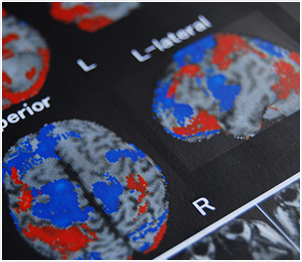

人間の脳や神経は、大雑把にいうと電気信号によってコントロールされており、脳や神経が働くときには、微弱な電流が流れます。

ですから、脳や神経は電気信号で動く「PC(パーソナルコンピューター)」だと見なすこともできます。実際のところ、脳や神経の働きは、適切に電気信号が入力され、それが適切に伝わっているかどうかで決まります。

PCの画像がときに乱れたり、バグが発生したりすることがあるように、脳や神経にも同様のトラブルが発生します。

不適切な電気信号(ノイズ、とも呼びます)に、脳や神経の働きを邪魔されると、脳細胞が通常とは別の働きを起こし、本来の目標達成には不要な信号を生み出してしまいます。